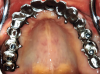

Fig 3. Maxillary arch after placement of TIs.

Figure 3

Placement of Transitional Implants

Teeth Nos. 10, 14, and 15 were extracted after achieving local anesthesia (2% lidocaine with 1:100,000 epinephrine, Henry Schein Dental). Teeth Nos. 6, 11, and 16 were retained as temporary abutments for the provisional. A midcrestal incision was made with a 15C blade, and a full-thickness flap was reflected with a periosteal elevator. Osteotomies were created with a 1.3-mm pilot drill at sites Nos. 3, 5, 8, 9, 12, and 14 using a surgical stent. Six TIs (Dentatus MTI, Dentatus) were placed using a right-angle handpiece driver and then tightened manually with the winged socket key (Figure 3).